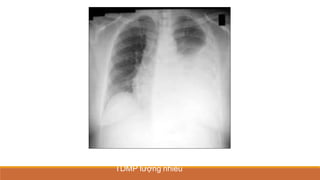

TDMP lượng nhiều